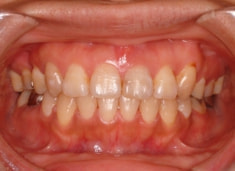

治療前